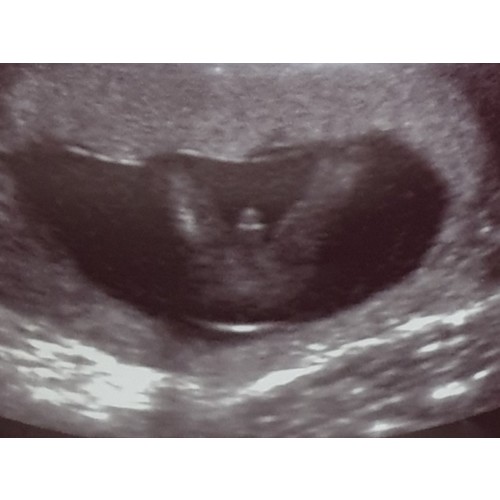

Dit is ook nog een foto

Overduidelijk een meisje, zou echt niet twijfelen 😉